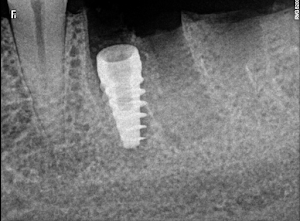

Welcome to our gallery

See how our company transforms ideas into reality. This gallery is a visual testament to our work and achievements.